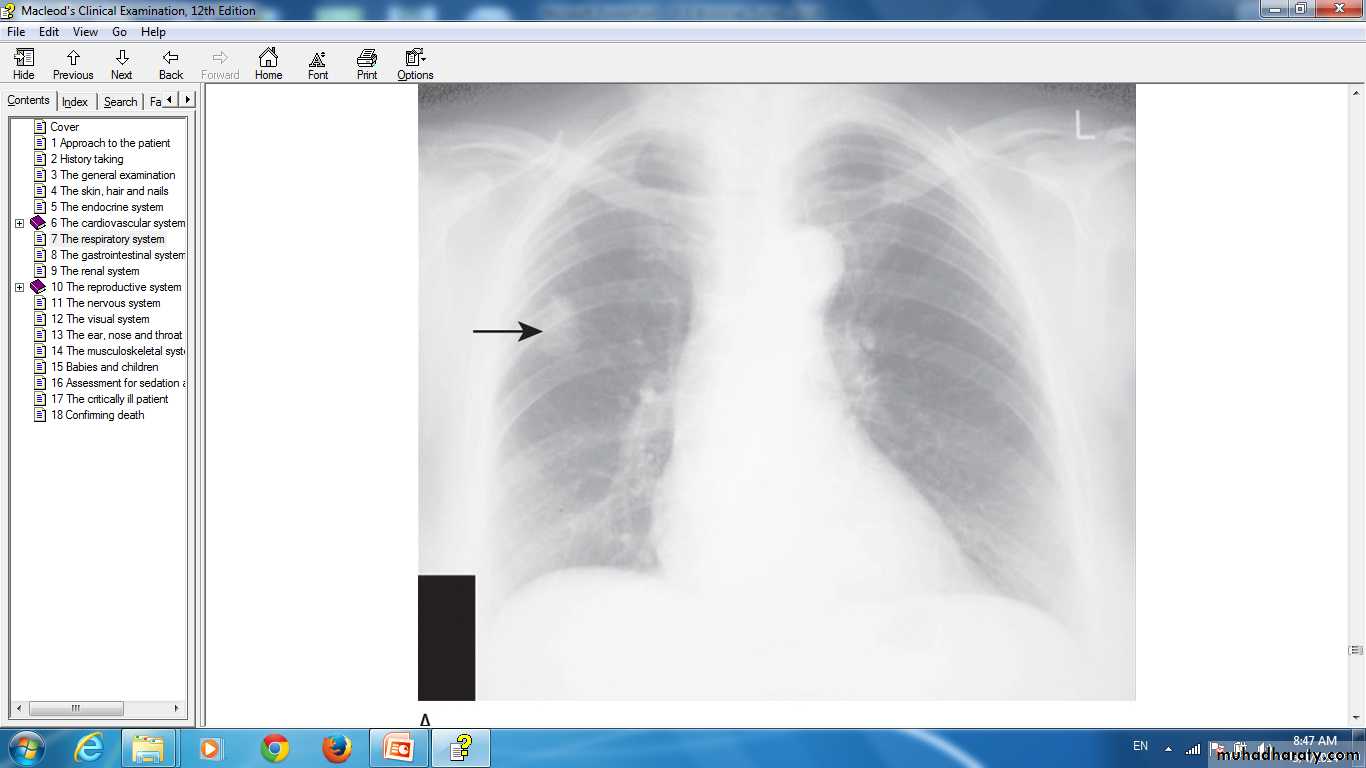

Lung cancer in right lung Chest X-ray.